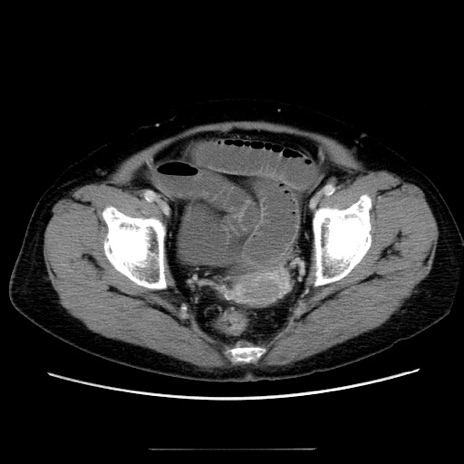

冠状断像

【症例】70歳代女性

【主訴】お腹が張る

【現病歴】1週間くらい前から腹部膨満の自覚あり。昨日夜から増悪したため、本日救急外来受診。

【身体所見】意識清明、BT 36.5℃、BP 165/106mmHg、HR 80bpm、SpO2 98%、腹部:膨満、軟、自発痛・圧痛なし、触診にて不快感あり、腸蠕動音:減弱

【データ】WBC 12600、CRP 1.04